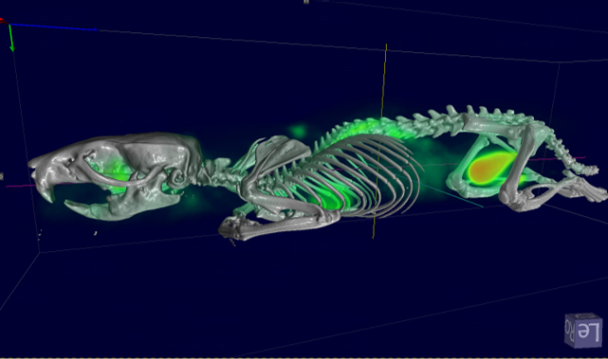

- Fully automated PET/CT stitched protocol, including attenuation correction (AC) map for rats up to 250 mm in length

Fast extended PET/CT imaging for full rat body coverage. Image Credit: Bruker BioSpin Group

Automatic MR-based Attenuation Correction (AC), calculating for animal cradle, MRI RF coil, and full animal body. Image Credit: Bruker BioSpin Group